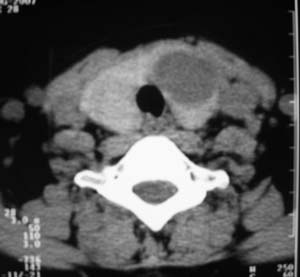

以下是引用zsl6918在2007-8-27 14:40:00的发言:[br]双侧甲状腺多发性低密度占位,边界清晰,密度欠均匀,尤以左侧明显,与周围组织分解清,考虑多发性腺瘤可能性大,不除外结节性甲状腺肿

以下是引用liaizhi在2007-8-27 15:20:00的发言:[br]双侧甲状腺散在多个囊性第密度影,左侧最大一个病灶与正常甲状腺分界尚可,气管受压稍右移。考虑甲状腺瘤的可能性大。